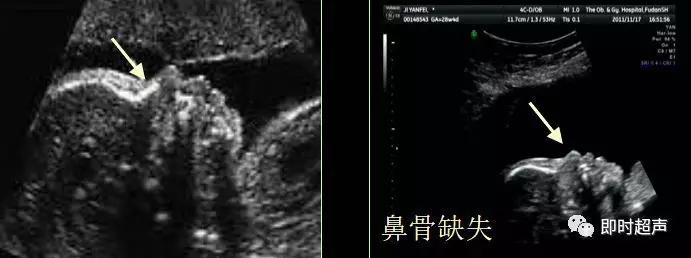

二、胎儿鼻骨(NB)

鼻骨发育不良

NB筛查时间:11—14周,异常标准:鼻骨缺失、鼻骨短小是染色体异常的超声指标。

超声鼻骨切面:正中矢状切面和横切面诊断鼻骨缺失时,至少需要在 2 个互相垂直的切面印证。

超声检查胎儿鼻骨可作为产前超声筛查的一个有效指标。

超声检查鼻骨临床价值:11-14周胎儿鼻骨检查的成功率为95%。21-三体的胎儿60-70%鼻骨缺失,中孕期 DS 组胎儿的鼻骨缺失发生率为 55.5%,而正常对照组为0.5%。